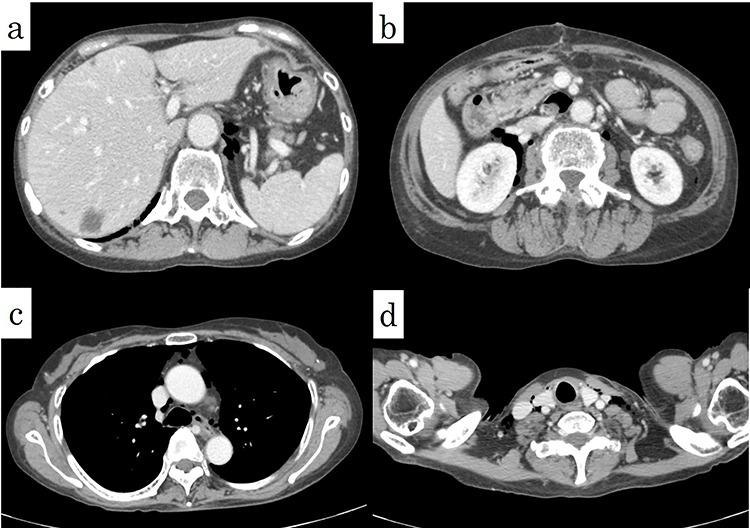

A 62-year-old woman had developed polymyositis 12 years previously and had taken oral steroids. Chest and abdominal computed tomography showed pneumomediastinum and free air in the abdominal cavity. Although a colon perforation was suspected, the perforation site could not be identified on the image. In addition, a diagnosis of oesophageal rupture could not be excluded from the findings of pneumomediastinum. After general anaesthesia, an upper gastrointestinal endoscopy was performed before surgery. Because there was no obvious perforation in the oesophagus, a laparotomy approach was used. A perforation was found on the mesentery side of the sigmoid colon, and a perforation of the sigmoid colon's diverticulum towards the mesentery was diagnosed. A Hartmann's procedure was performed. Colon perforations are rarely associated with pneumomediastinum. Preoperative endoscopy is useful to help diagnose and determine the surgical procedure if an obvious perforation cannot be identified.